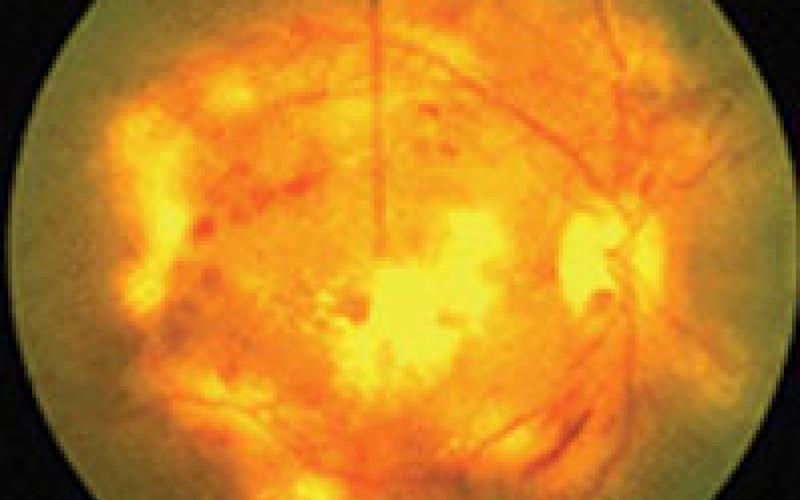

Retina Ven Tıkanıklığı

Normal FFA

Anormal FFA